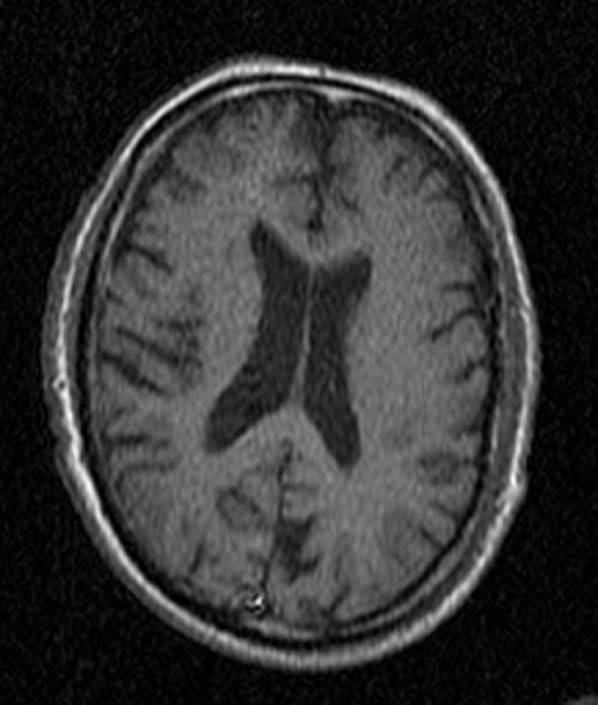

CT: Brain Atrophy